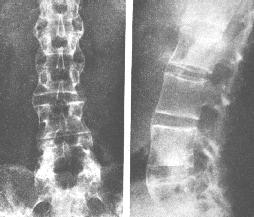

陽性。3.退變性骶髂關節炎

X線平片上顯示關節退變,視病程不同而出現退行性變的各期表現,以增生及骨刺為主。治療方法